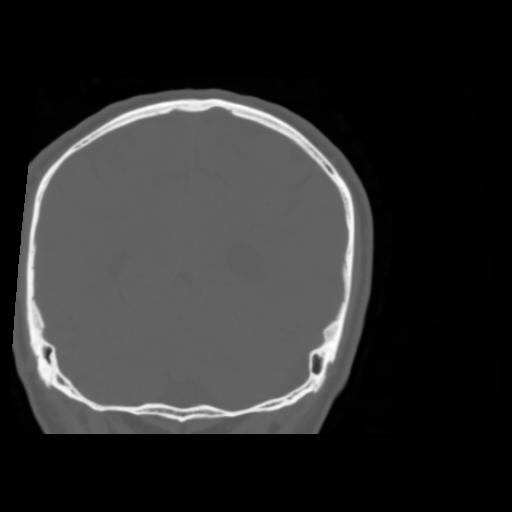

5 CEREBRO,,Coronal,3.000,CEREBRO,Coronal,